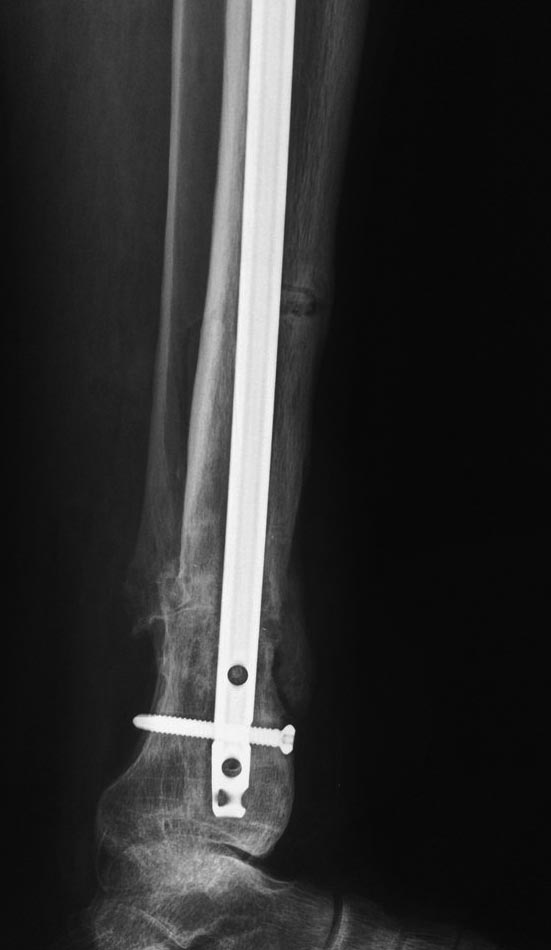

Уважаемые коллеги выразите Ваше мнение по следующему случаю.Молодой человек, 27 лет, находится на лечении с диагнозом: Ложный сустав большеберцовой кости в нижней трети, фиксированный интрамедуллярным блокированным стержнем (12.02.2014 г), ложный сустав малоберцовой кости в нижней трети левой голени, посттравматический артроз левого голеностопного сустава 1 стадии. Укорочение левой нижней конечности на 1,0 см. Со слов пациента известно, что в детстве получил перелом большеберцовой кости, лечился консервативно, перелом сросся с деформацией. Травма в июле 2010 г. бытовая-упал на лестнице, получил перелом малоберцовой кости, и перелом большеберцовой кости без смещения. Выполнена операция: Остеотомия большеберцовой кости в нижней трети, интрамедуллярный блокированный остеосинтез большеберцовой кости левой голени. Гладкое течение послеоперационного периода. Перелом большеберцовой кости сросся. Функция конечности восстановилась. В июне 2013 г выполнена операция удаление интрамедуллярного стержня из большеберцовой кости левой голени. Гладкое течение послеоперационного периода. Приступил к занятием физкультурой, бег. В августе 2013 г спрыгнул с автобуса, с чемоданом в руках, появилась резкая боль в левой голени. За медицинской помощью обратился через 7 дней, при обследовании выявлено: Рефрактура большеберцовой кости. Рекомендовано консервативное лечение в гипсовой повязке. В январе 2014 г. установлен диагноз: Ложный сустав большеберцовой кости в нижней трети, малоберцовой кости в нижней трети левой голени. Контрактура сгибательно - разгибательная левого голеностопного сустава. Посттравматический артроз левого голеностопного сустава 1 стадии. Укорочение левой нижней конечности на 1,0 см. В феврале 2014 г выполнил первым этапом: Фиксацию ложного сустава в АНФ с восстановлением осей сегментов. Через семь дней БИОС с рассверливанием. После операции - вальгус голеностопного сустава. Гладкое течение послеоперационного периода. Нагрузка по переносимости боли. Через 6 недель динамизация, через 2 недели стали мигрировать 2 фронтальных винта. Пытался подкрутить, пришлось удалить. Через 6 мес., контроль - линия ложного сустава прослеживается, но имеется периостальная костная мозоль. Не хватает стабильности.Вопрос что делать?Вариант № 1- выполнить реостеосинтез с рассверливанием КМК и на 12 мм диаметра гвоздь (стоит 11 мм)и убрать ротацию стопы руками одномоментно или одномоментно при помощи АНФ во время операции. Вариант № 2 выполнить удаление гвоздя, сделать все то же, что 6 месяцев назад, но с восстановлением анатомических взаимоотношений в голеностопном суставе.Вариант № 3 Двухэтапно, вторым этапом пластина на большеберцовую кость + костная пластика области не сращения.Вариант № 4 удаление гвоздя и лечение в КДА. Вопросы:1. Какой вариант оперативного лечения будет оптимальным в данном случае.2. При двухэтапной методике в дистальном отломке имеется канал от гвоздя, как направить гвоздь к наружному отделу дистального отломка большеберцовой кости. Есть опасения, что гвоздик может пойти по тому же каналу. Использовать поллер спицы или винты – сработают ли? И достаточна ли будет жесткость фиксации дистального отломка большеберцовой кости на гвоздике при 3 – 4 винтах при реостеосинтезе гвоздем.3. Нужен ли остеосинтез малоберцовой кости в нижней трети, с целью создания латеральной опоры. К сообществу за советом.

Здесь можно использовать все названные варианты. Гвоздь вполне тоже можно. Надо аппаратом восстановить длину и не повторять прежней ошибки - надо латеральную стенку сопоставить, а не оставлять наружного смещения. Да, надо ввести передне-задние спицы, чтобы не дать стержню попасть в старый канал. И длинной ручной разверткой лучше бы сформировать новый канал.

Возможно, не все снимки выставлены, потому что не нашел признаков проведенной динамизации, о которой писали. Верхние винты остались нетронутыми, трудно опознать динамизацию. По поводу применения “cap” на гвозде имеется сомнение, потому что высоко расположенный по верхнему краю гвоздь не позволяет воспроизвести динамизацию. Перед динамизацией надо укорачивать гвоздь или убирать “кап”.

По поводу лечения, проблем правильной установки гвоздя не будет. Можно с помощью поллеров, которые помогут вывести в нужную траекторию. Но, если прежние попытки не привели к успеху, стоит ли тогда повторить неудачный опыт? Какая гарантия, что вальгусные силы не деформирует ось. Надо пересмотреть иллюзию, что гвоздь является идеальным фиксатором для решения данной патологии! Еще, при попытке подвести проблему под определенный фиксатор, результат получается неутешительным!

Из предложенных, я бы остановился на третьем варианте. Основная работа должна быть против вальгуса, и медиальная пластина для этой роли не подходит. Передний доступ, остеотомия большой и малоберцовой. Сагиттальная пила для артропластики толстая и не экономит кость. Полотно не более, чем 1.1 мм толщиной, создает идеальную поверхность остеотомии. Затем боковая компрессия-лагированием и передная пластина с костным графтом! Возможно, потеряет часть высоты, но наконец то возникнет сращение!